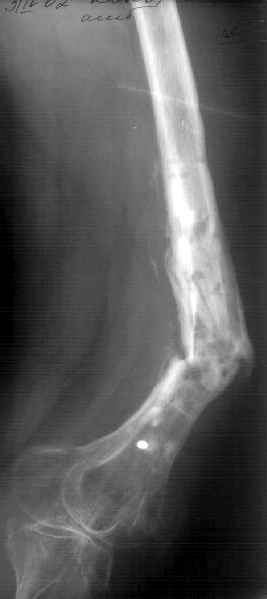

К нам поступила худощавая женщина 48 лет, которой года 2,5 назад был выполнен остеосинтез бедра пластинкой в одной из горбольниц. В сентябре 2001 г. пластинку убрали. Начала разрабатывать движения, ходила с тростью. С января этого года

отмечает усугубление деформации бедра и улучшение движений "в коленном суставе". При осмотре имеетсяподвижность на месте перелома (псевдартроза), больше в сагиттальной плоскости. Рентгенограммы в приложении(фас; профиль). Полностью угол, открытый кзади, под нагрузкой не устраняется. "Сгибается" еще градусов на 30. Ходит с тростью. Надколенник неподвижен, в суставе, видимо, движений нет совсем. В любом случае надо, видимо, начинать с восстановления оси и стабилизации бедра. Как окончательный фиксатор хотелось бы использовать интрамедуллярный стержень. Можно ли в данном случае устранить угол одномоментно? Или лучше дозированно? Нужна ли костная пластика местно? Не стоит ли пойти на мобилизующую операцию в один этап? Если да, то какую?Может быть, есть еще какие-то моменты, которые следует учесть?Спасибо заранее.-- Best regards, Alexander N. Chelnokov

The pt has 20 degree of varus and 30-40 degree of procurvatum Acute correction may compromise the nurovascualr structures. Moreover xray shows evidence of infection and she has almost knee range of motion.

In such a case I would suggest a gradual correction with an ILIZAROV frame as an oblique plane defoemity.

Не сформировалось у нас убежденности в целесообразности мобилизующей операции в один этап с остеосинтезом. Решили пойти по максимально щадящему пути. Первым этапом наложили аппарат. Снимок (см. приложение) сделан в положении максимально возможной коррекции оси, достигаемой одномоментно исправлением "об коленку" с ручным растягиванием колец сзади. Варус удалось убрать, а вот антекурвацию, от греха, лучше устраним дозированно, дней за 7-10. Потом планируем антеградный закрытый интрамедуллярный остесинтез. Буду признателен за отклик.